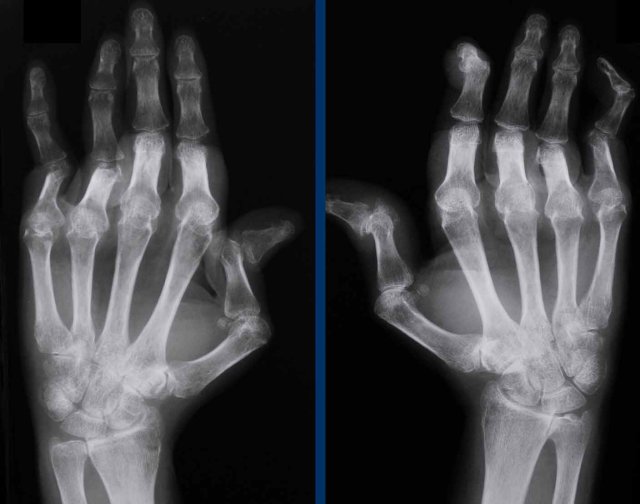

End stage Rheumatoid arthritis. End stage Rheumatoid arthritis.

This is a case with end stage rheumatoid arthritis with severe erosive changes and ligamentous ruptures causing dislocation of the MCP joints.

Scapholunate dissociation (white arrow) is a common finding due to diffuse carpal inflammation. Both the dissociation and inflammation can cause joint space narrowing in the radiocarpal joint.

Notice also the erosion in the distal ulna with surrounding soft tissue swelling (blue arrow).

Rheumatoid arthritis in the feet Rheumatoid arthritis in the feet

In this case of rheumatoid arthritis there are marginal erosions adjacent to almost all MTP joints (arrowheads).

The 5th MTP joint is most frequently involved in  rheumatoid arthritis.

When erosions are as severe as in this case, it can look like pencil-in-cup deformity (white arrow) as is frequently seen in psoriatic arthritis.

However, the primarily affected MTP joints distribution and less affected interphalangeal joints is the clue that this is a case of rheumatoid arthritis.